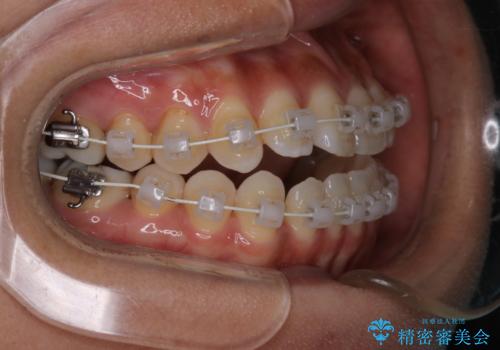

- 開咬を主訴に来院されました。前歯部に開咬、右側大臼歯部にクロスバイトが認められます。ワイヤー矯正の審美装置で治療し、ゴム掛けを行いながら噛み合わせを改善しました。

主訴である開咬と右側大臼歯部クロスバイトを改善でき、しっかりと噛むことができるようになりました。